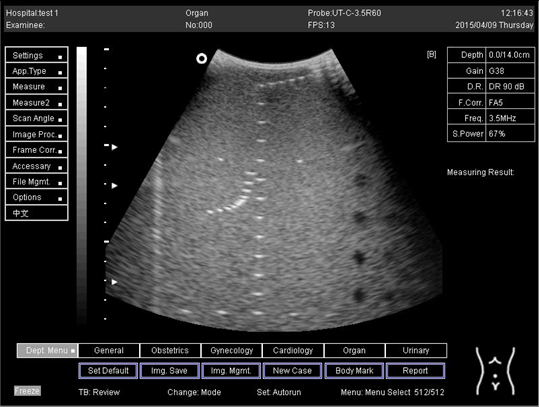

In the current experiment, tissue-simulating phantom quality assurance was applied to examine the performance and accuracy of the ultrasound imaging device (Figure 1). The phantom simulates the acoustic features of real tissue and supports the measurement of structures in an encouraging environment. The imaging system can detect any alterations in performance that happen during the ordinary lifetime of imaging system parts. Thus, routine examination control is able to minimize the time of repeat scans and maintenance duration.

Figure 1. Multipurpose phantom model 539.